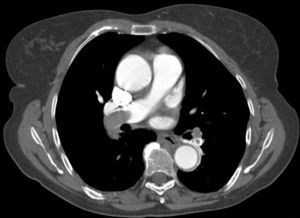

Estudo imagiológicoAs imagens de TCMD foram adquiridas na direção craniocaudal (colimação de 1,25mm), permitindo uma avaliação precisa das artérias pulmonares principais, lobares, segmentares e subsegmentares, ao nível dos lobos inferiores, médios e superiores.

Um bólus de 120mL de contraste iodado (concentração de 350mg/mL) foi injetado na veia antecubital esquerda (quando possível) a uma taxa de 4ml/s, utilizando um injetor automático.

As imagens foram revistas por 2 radiologistas numa workstation de modo independente, desconhecendo as variáveis clínicas, exames complementares e prognóstico intra-hospitalar dos pacientes.

Para além da avaliação da carga embólica na TCMD, foram efetuadas medições quantitativas dos diâmetros das estruturas vasculares (VCS e VA) e cardíacas (VD, VE, ratio VD/VE; SC, AP, Ao, ratio Ap/Ao) relacionadas com a árvore pulmonar. O desvio do SIV e o refluxo de contraste na veia cava inferior (VCI) foram avaliados qualitativamente, de forma a definir os sinais de DVD (Figuras 2-5).